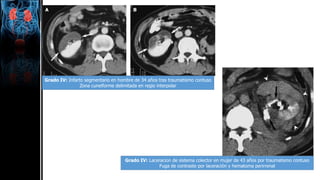

Grado IV: Infarto segmentario en hombre de 34 años tras traumatismo contuso

Zona cuneiforme delimitada en regio interpolar

Grado IV: Laceracion de sistema colector en mujer de 43 años por traumatismo contuso

Fuga de contraste por laceración y hematoma perirrenal